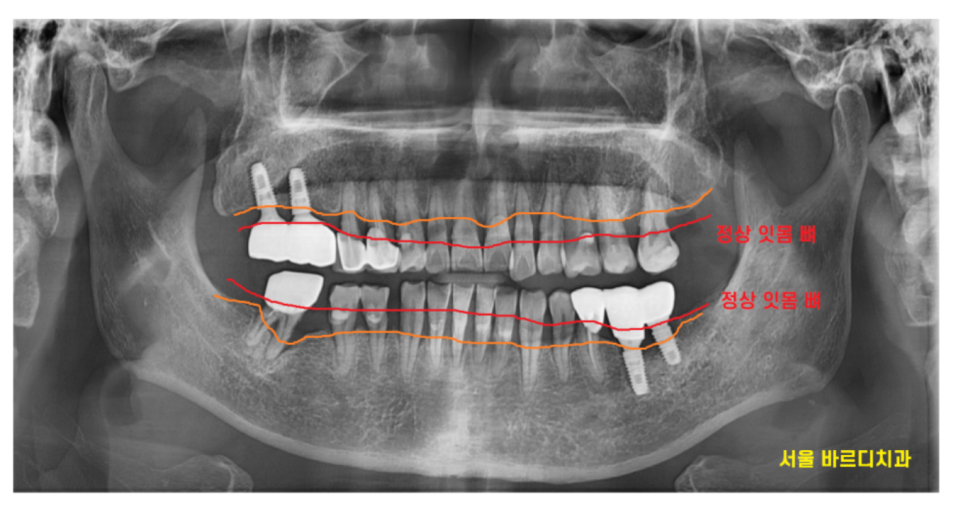

240423 치아가 빠진쪽으로 기울어져있죠?

치아 한두개 없다고 식사가 안되는 것도 아니고

일하느라 바쁘다보니

가야지... 마음만 먹게되는게 현실인데요.

그런 와중에도 치아는 계속 안좋아지고 있답니다.

<치아 상실을 방치했을 때 문제점>

인접 주변 치아가 옆으로 쓰러지고

맞물리는 치아가 내려오거나 올라오고

남은 치아에 과도한 힘이 실리고

치아 빠진 부위의 잇몸뼈는 흡수가 빨리되고

결과적으로 남은 멀쩡한 치아마저 망가지고,

더 빨리 무너집니다.

처음 작은 문제가 전체적인 구강 건강을 위협하게 되는 셈이죠.

250326 잇몸뼈가 녹은 부위는 까맣게 관찰됩니다.